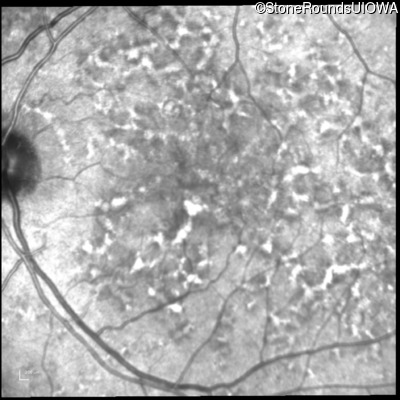

Fluorescein Angiography - Right - 20/40 +2 sc

Exemplar